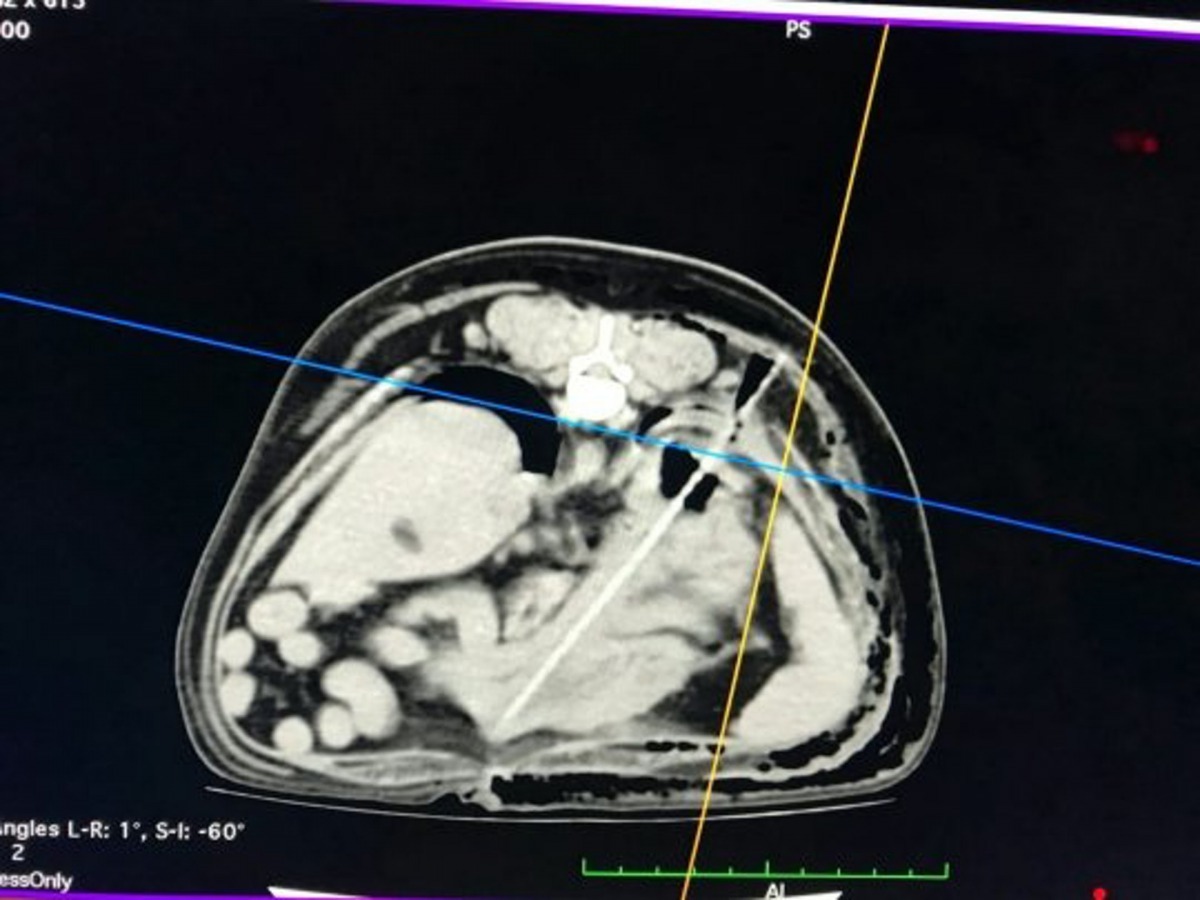

由於實在太奇怪,Sharon在和丈夫商討後,決定第二天一早就帶Monty去看獸醫。獸醫指Monty沒有任何表面的傷痕,但經過電腦斷層掃描(CT掃描)後,發現牠胸腔裡有一根長長的物體,已刺穿了牠的橫膈膜和肺部,情況相當不妙,要立即動手術移除。

當時Sharon嚇得歇斯底里,Monty是她最重要的寶貝。她當然答應動手術,但直到手術結束,他們才知道那細長物體,原來是一根烤肉的竹籤!而手術後,Sharon收到了手術帳單,竟要6000英鎊,但對Sharon來說是值得的。她猜測Monty一定是趁著外出散步時,偷偷亂吃路旁的東西,而且是狼吞虎嚥,不留痕跡,不然沒可能不察覺。希望經過今次教訓後,Monty能學乖別亂吃東西了!